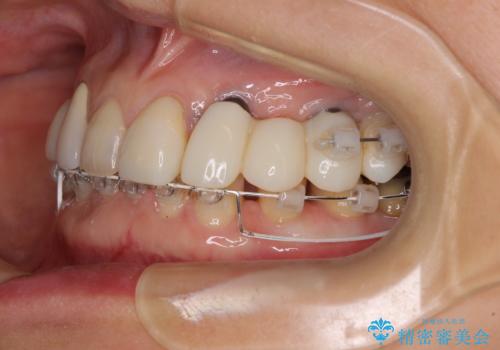

- 割れていると言われて放置してしまった歯や、前歯のデコボコなどが気になるとのことで来院された患者様です。

左上の歯は割れてしまっており、抜歯のうえインプラント治療が必要であり、他にも抜歯の必要な歯がある状態でした。

上顎はほぼ全ての歯をセラミッククラウンにて補綴治療を行う必要があるため、気になるデコボコや深い咬み合わせを改善するために下顎と上顎の臼歯部の矯正治療を行うこととしました。

並行して左下にはインプラントを埋入し、矯正治療を終えると同時に補綴治療を行うこととしました。

過蓋咬合(下顎前歯が隠れてしまうほどの深い咬み合わせ)のため、スムーズに歯が動かず矯正治療に時間がかかりましたが、無事に仕上げることができました。